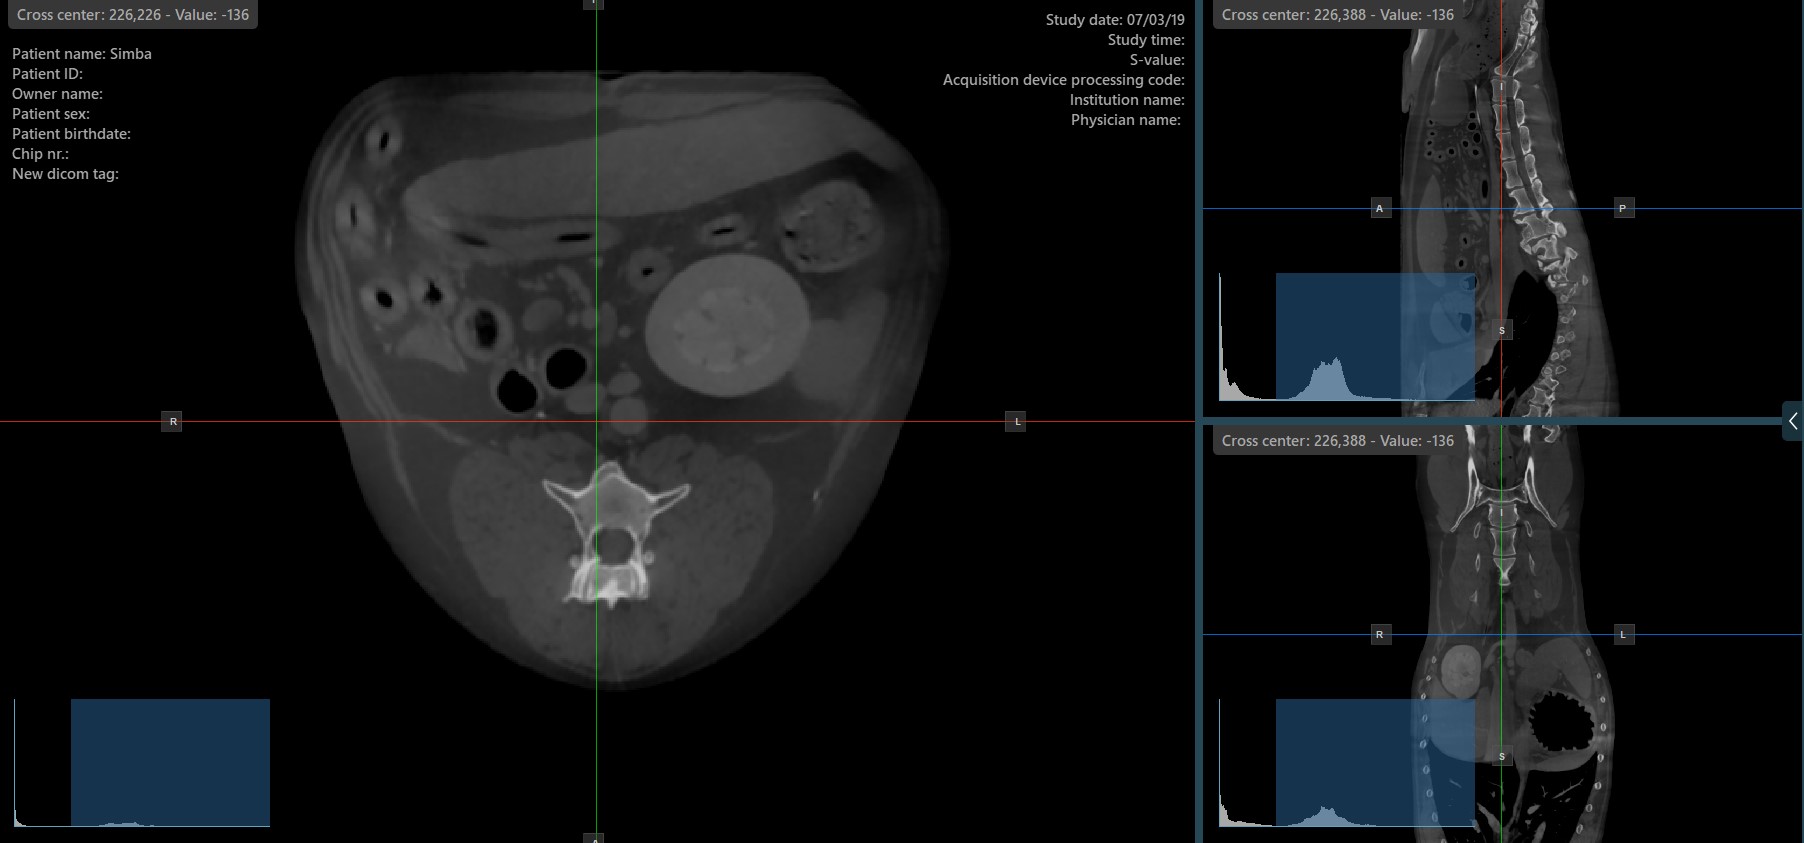

The slicers in MPR view show the intersections and orientation of the three image planes displayed in the active viewports. Users can modify the slicers and change the cross-sectional position of the slices based on the 3D volumetric data.

Each slicers is distinguished by their specific color, which representes the image plane:

The blue slicer marks the axial plane of the object (perpendicular to the ground)

The red slicer marks the coronal plane (parallel to the ground)

The green slicer marks the sagittal plane (perpendicular to the body)

By default, the slicers are visible on the top of the images. The corresponding icon in the left toolbar of the CT Viewer will be selected when the slicers are visible.